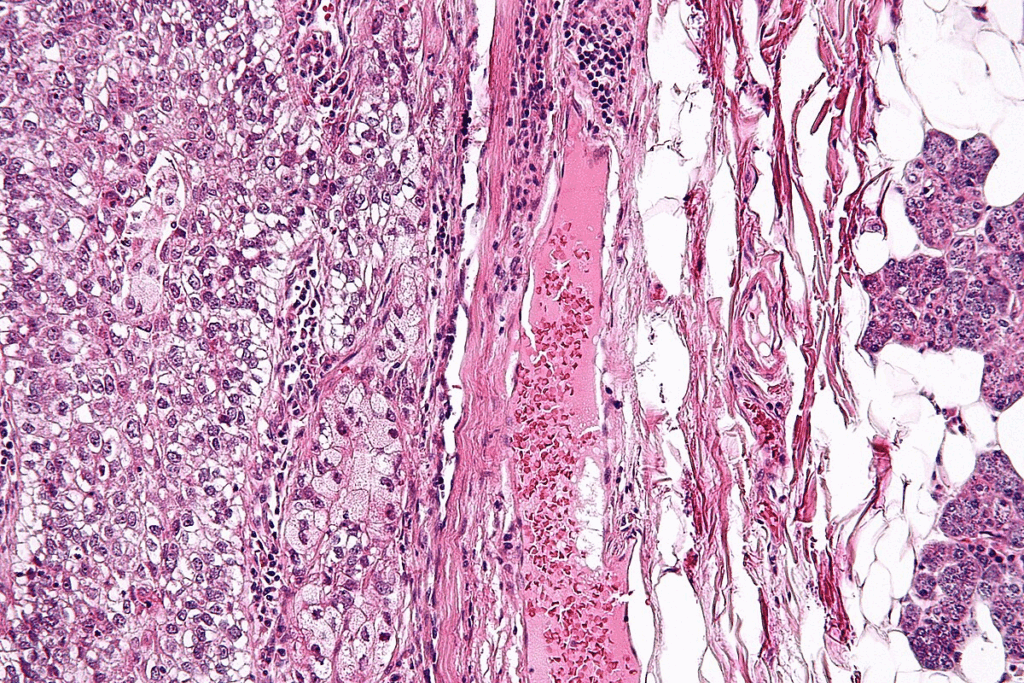

Morphoeic Basal Cell Carcinoma: The Invasive Subtype

Morphoeic basal cell carcinoma is a tough type of BCC to diagnose. It has scar-like appearance that makes it hard to tell apart from other skin issues.

This type of BCC looks like a flat, hard scar. It’s often mistaken for a normal scar, leading to late diagnosis.

Scar-like Appearance and Poorly Defined Borders

The morphoeic subtype of basal cell carcinoma is known for its:

• Flat, scar-like appearance

• Poorly defined borders, making it challenging to determine the extent of the lesion

• Potential for significant local destruction if left untreated

These traits mean it needs a detailed check-up. Sometimes, extra tools are needed to see how big the cancer is.

Why This Type Requires Special Attention

Morphoeic basal cell carcinoma needs extra care because of its:

1. Aggressive growth pattern

2. High risk of local recurrence if not adequately treated

3. Potential for significant disfigurement if diagnosis is delayed

Early detection and the right treatment are key. A detailed plan, like surgery with careful margin control, helps avoid problems.